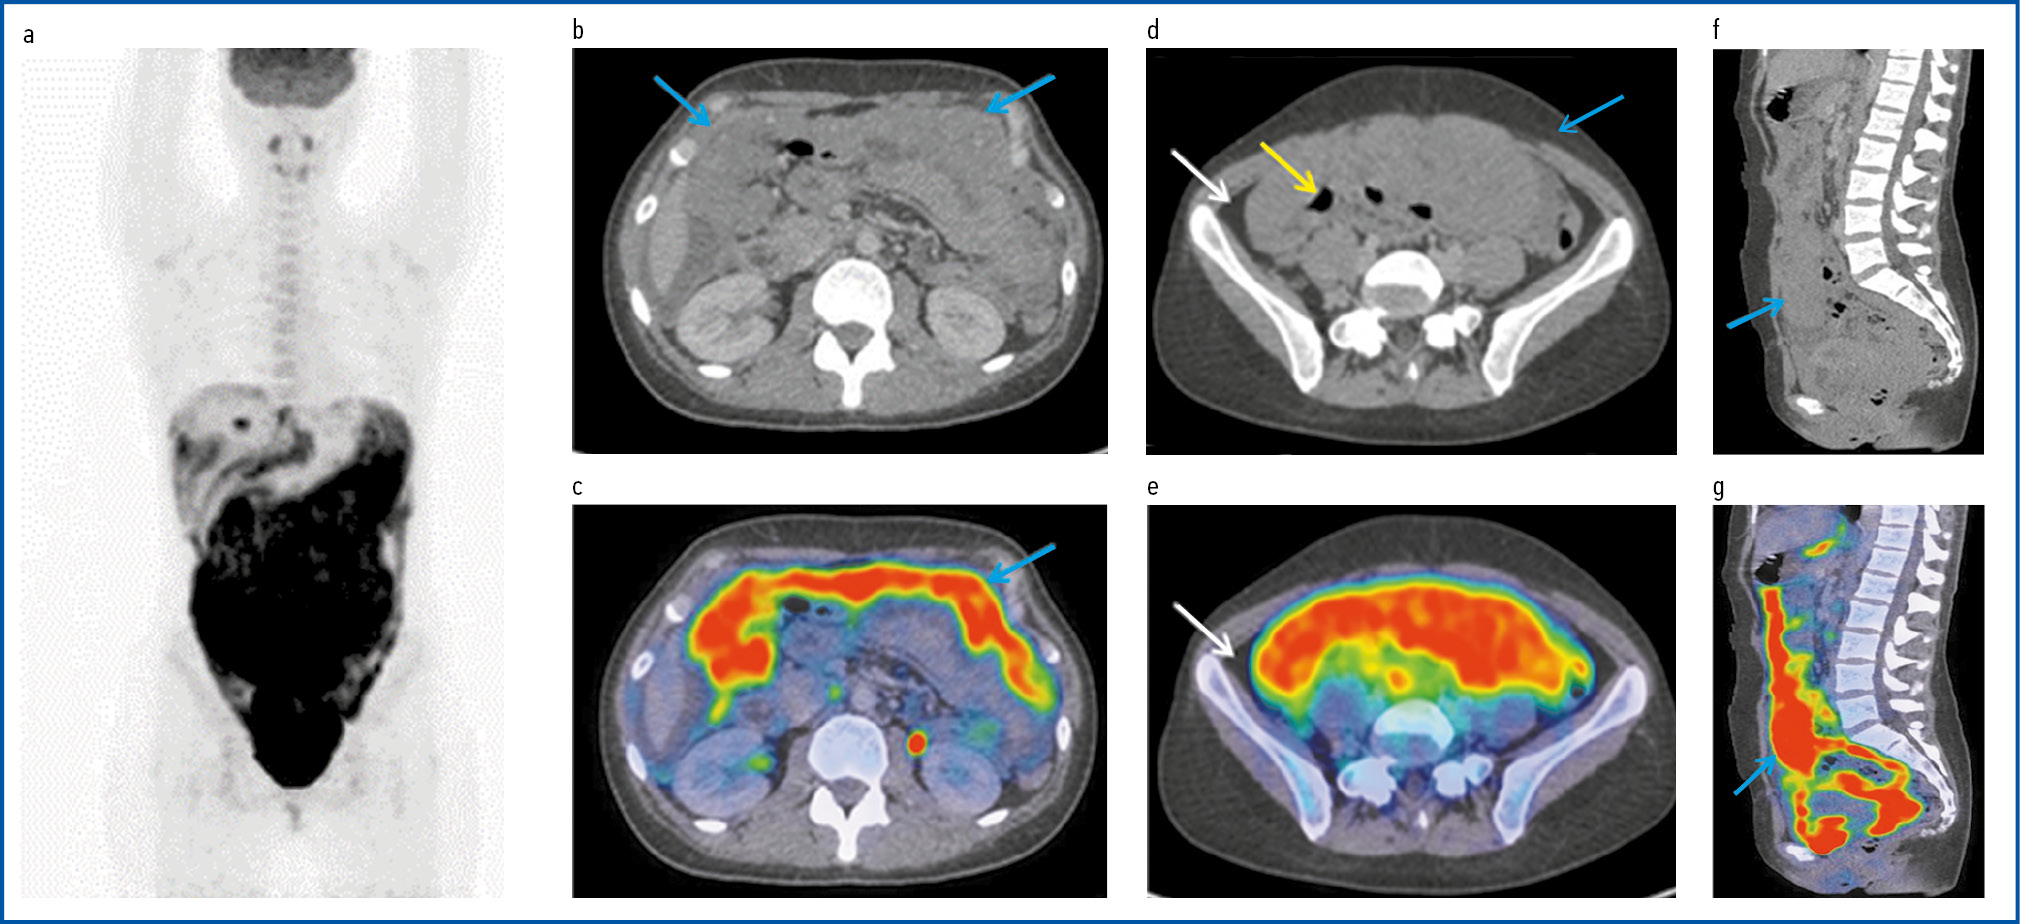

Рис. 2. Пациентка Н., 23 г. На серии MIP ПЭТ (а) и совмещенных ПЭТ/КТ аксиальных проекциях (b–e), сагиттальных проекциях (f, g) отмечается диффузное уплотнение брюшины, сальниковой и межорганной абдоминальной клетчатки с активным субтотальным заполнением брюшной полости и малого таза опухолевой массой с повышенной фиксацией РФП, SUVmax 14,5 (голубые стрелки). Патологическая ткань непрерывно распространяется по ходу брюшины и капсуле печени и селезенки. Петли кишечника в толще опухолевой массы дифференцируются фрагментарно (желтая стрелка). В паренхиме печени и селезенке ФДГ-активных очагов поражения не обнаружено. На КТ аксиальной проекции (b, d) перигепатически, перилиенально по правому и левому фланку определяется скопление жидкости (белые стрелки).

Fig. 2. Patient N., 23 years old. On the MIP PET series (a) and combined PET/CT axial views (b–e), sagittal views (f, g), diffuse compaction of the peritoneum, omentum, and interorgan abdominal tissue with subtotal filling of the abdominal and pelvic cavity with a tumor mass with increased radiopharmaceutical uptake, SUVmax 14.5 (blue arrows). Abnormal tissue continuously spreads along the peritoneum and capsule of the liver and spleen. The intestinal loops differentiate fragmentarily within the tumor mass (yellow arrow). No FDG-active lesions were detected in the liver and spleen parenchyma. CT scan of the axial view (b, d) showed the accumulation of fluid (white arrows) around the liver and spleen along the right and left flanks.

Для уточнения распространенности опухолевого процесса и выработки тактики лечения больной выполнена ПЭТ/КТ с 18-ФДГ. Согласно полученным данным на ПЭТ-изображениях проекции максимальной интенсивности и объединенных ПЭТ/КТ-проекциях определяется диффузное утолщение брюшины, сальника без образования узлов, межорганной клетчатки и брыжейки с повышенной метаболической активностью 18-ФДГ. Брюшная полость и малый таз субтотально заполнены опухолевой массой с гиперметаболизмом 18-ФДГ, стандартизированный коэффициент максимального накопления (SUVmax) равен 14,5. Активность непрерывно распространяется по ходу брюшины с переходом на капсулу печени и селезенки. В паренхиме указанных органов очагов поражения не выявлено. Объединенные ПЭТ/КТ-изображения также не показывают поглощение радиофармпрепарата (РФП) в тонком и толстом кишечнике (рис. 2).

Мезентериальные лимфатические узлы не дифференцируются за счет сливного включения в опухолевые массы. Повышенной фиксации РФП в костном мозге не выявлено. Метаболической активности в периферических и медиастинальных лимфоузлах нет. Имеется умеренный асцит.

Согласно результатам ПЭТ/КТ с 18-ФДГ у пациентки Н. имелась высокая авидность к 18-ФДГ, которую следует трактовать как диффузный метаболический тип с патологическим распространением по париетальному и висцеральному листкам брюшины, брыжейки и сальника.

В представленном нами случае у пациентки имелись незначительный асцит, диффузное поражение париетального и висцерального листков брюшины, сальника и брыжейки с поражением мезентериальных лимфоузлов, а также массивное заполнение брюшной полости и малого таза опухолевой массой с повышенной фиксацией РФП, SUVmax составлял 14,5.